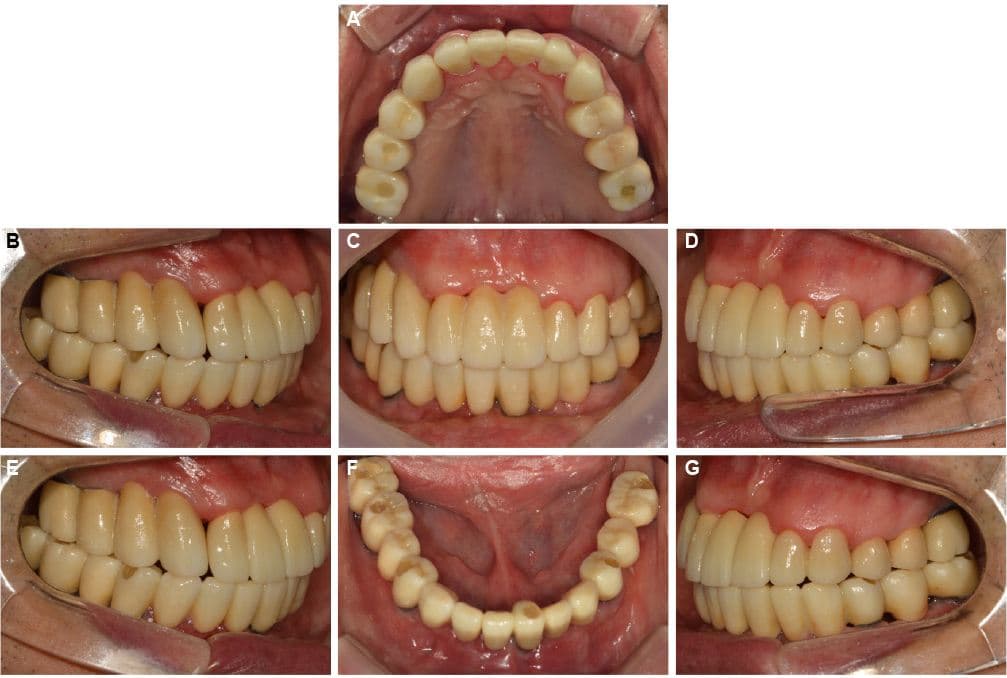

Complex Cases

Full Mouth Reconstruction

Before & After

Cases of completely damaged oral health

restored to normal daily life

Comprehensive Treatment by Prosthodontist

Full Mouth Reconstruction · Mr. S●● · Male, 70s

Full Mouth Reconstruction · Mr. O●● · Male, 60s